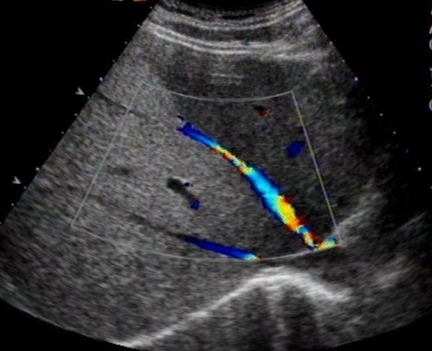

(7)符合影响诊断学。如超声显示:肝区近场弥漫性点状高回声(肝区回声密集增强),远场(或后方)回声衰减。

(4)其首选检查是超声,其超声表现和非酒精性肝病极其相似。确诊的方法用肝穿刺活组织检查。